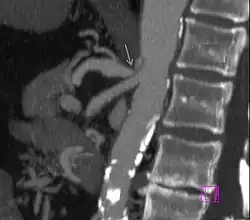

Die CTA zeigt die Verengung (Pfeil) des Truncus coeliacus

Die Befunde einer kurzstreckigen Einengung des Truncus coeliacus an seinem Abgang mit nachfolgender Erweiterung (poststenotische Dilatation), einer Einkerbung im oberen Aspekt des Truncus und eines hakenförmigen Verlaufes des Truncus unterstützen die Diagnose eines Truncus-coeliacus-Kompressionssyndroms.[1] Diese Bildkriterien sind in Exspiration betont und finden sich zum Teil sogar bei asymptomatischen Patienten, die nicht an dem Syndrom leiden.[1]

Auch müssen andere mögliche Differenzialdiagnosen bei einer abgangsnahen Einengung mit poststenotischer Dilatation, wie zum Beispiel arteriosklerotische Veränderungen, berücksichtigt werden.[1] Hier kann der hakenförmige Verlauf des Truncus coeliacus für die Unterscheidung hilfreich sein, wenn auch dieses Kriterium ebenfalls nicht pathognomonisch für das Truncus-coeliacus-Kompressionssyndrom ist. Die Häufigkeit für diese Anatomie bei normalen asymptomatischen Personen wird mit 10 bis 24 % angegeben.[1]